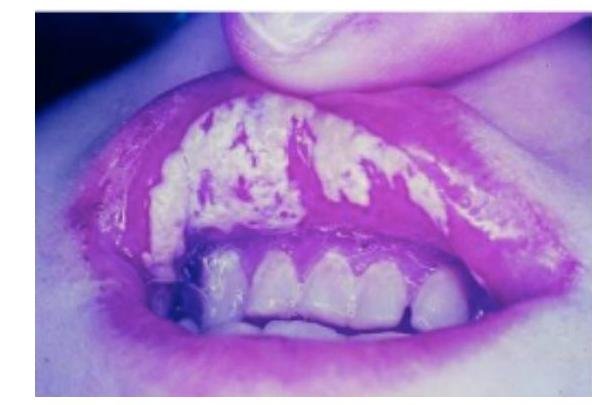

# VIH - CLÍNICA ## **PRIMOINFECCIÓN** En un principio, la **infección por VIH** primaria puede ser asintomática o causar síntomas inespecíficos transitorios (**síndrome retroviral agudo**). ## SÍNDROME RETROVIRAL AGUDO Puede comenzar entre la 1ª y 4ª semana de la infección y durar entre 3 y 14 días. Los síntomas y signos a menudo se confunden con los de la mononucleosis infecciosa o con síndromes virales benignos inespecíficos. - Fiebre (96%) - Linfadenopatía (74%) - Faringitis (70%) - Exantema (70%) - Mialgias y Artralgias (54%) - Diarrea (32%) - Cefalea (32%) - Malestar General - Fatiga - Meningitis Séptica. Después de la desaparición de los primeros síntomas, la mayoría de los pacientes no presenta síntomas o solo manifiesta pocos síntomas inespecíficos leves e intermitentes, durante un **período muy variable** (entre **2 y 15 años**). Durante este periodo pueden presentarse síntomas insidiosos: - Linfadenopatías - Placas orales blancas provocadas por candidiasis oral - Herpes zóster - Diarrea - Cansancio - Fiebre con sudoración intermitente  ## **PROGRESIÓN** | Progresor Típico (80%) | Libres de síntomas hasta 5-10 años después de la infección. | | :-- | :-- | | Progresor Rápido (10-15%) | Inicio de síntomas en los primeros 5 años tras la **primoinfección**. | # SIDA El **Síndrome de Inmunodeficiencia Adquirida** es la etapa avanzada de la **infección por el VIH** y se define por el desarrollo de diversas **infecciones oportunistas**, **cánceres** o por un recuento de **CD4** < 200/ \mu L. ## CONDICIONES QUE DEFINEN EL SÍNDROME DE INMUNODEFICIENCIA ADQUIRIDA (SIDA) - Infecciones bacterianas múltiples o recurrentes (solo en niños menores de 6 años) - Candidiasis en bronquios, tráquea o pulmones - Candidiasis en esófago - CaCu Invasivo - Coccidioidomicosis diseminada o extrapulmonar - Criptococosis extrapulmonar - Criptosporidiosis intestinal crónica (>1 mes de duración) - Enfermedad por CMV (distinta de hígado, bazo o ganglios) - Retinitis por CMV - Encefalopatía relacionada al VIH - Herpes Simple con úlceras crónicas >1 mes de evolución o con bronquitis o neumonitis por Herpes Simple - Histoplasmosis diseminada o extrapulmonar - Isosporiasis intestinal crónica (>1 mes de duración) - Sarcoma de Kaposi (Herpes Virus 8) - Linfoma de Burkitt - Linfoma Inmunoblástico - Linfoma primario del cerebro - Complejo de Mycobacterium avium o Mycobacterium kansasii; diseminado o extrapulmonar - Mycobacterium tuberculosis de cualquier sitio (pulmonar, diseminada o extrapulmonar) - Mycobacterium de especies no identificadas - Pneumocystis de jirovecii (antes llamado Pneumocystis carinii) - Leucoencefalopatía multifocal progresiva - Toxoplasmosis del cerebro - Síndrome de emaciación del VIH  # DIAGNÓSTICO ## **CONFIRMACIÓN** Cuando se sospecha de **infección por el VIH**, al identificar factores de riesgo y comorbilidades, solicitar una prueba de **ELISA** para **VIH**, y de ser positiva, realizar una prueba confirmatoria. ## PRUEBA RÁPIDA - Detecta anticuerpos en sangre total o plasma - La positividad se da en menos de 20 minutos. - Sensibilidad y especificidad 99% en infección crónica. En infección aguda falla en un 12%. ## ELISA Los ensayos de anticuerpos inmunoabsorbentes ligados a enzimas (**ELISA**) de 1ª generación son muy sensibles, pero ya que no analizan el **antígeno**, no son positivos tan pronto como la prueba combinada de 4ª generación. - Ante una primera prueba negativa y persistir sospecha, repetir **ELISA** en 3 meses. - Si se realizan dos **ELISA** con resultado positivo, se deberá confirmar por **Western Blot**. ## WESTERN BLOT Prueba confirmatoria para establecer el **diagnóstico** de **infección por VIH**. Detecta **Gp10**, **Gp41**, **p28**. ## **DIAGNÓSTICO DE VIH** = dos **ELISA** positivas + **Western Blot** confirmatorio ## PCR La detección del **ADN proviral** se utiliza para valorar la **transmisión vertical madre-hijo** y para el seguimiento de la **profilaxis post-exposición**. # EVALUACIÓN Los estudios que deben incluirse en la **evaluación inicial** de un paciente con **infección por el VIH/SIDA** para **estadificar la enfermedad** y apoyar la selección del **esquema ARV** son: - Anticuerpos para el **VIH** (**ELISA**) - Cuenta de Linfocitos T **CD4+** - **Carga Viral RNA-VIH** - Biometría hemática completa - Química sanguínea, pruebas de función hepática (**transaminasas**, **nitrógeno ureico**, **creatinina**), examen general de orina y depuración de **creatina** de 24 horas. - **Glucosa** y **Perfil de lípidos** que incluya **cHDL**, **cLDL**. - **BÚSQUEDA DE INFECCIONES**: serología para **Hepatitis A, B y C**, **Citomegalovirus**, **VDRL** (**Sífilis**), **Toxoplasma**, **Gonorrea**, **Chlamydia** y **PPD** (**Tuberculosis**). - En su caso, determinar el **alelo HLA-B\*5701**. ## RECUENTO DE LINFOCITOS T CD4+ El **recuento de linfocitos CD4+** absolutos y su porcentaje, es el principal indicador del **estado inmunológico** del paciente con **infección por el VIH**. Se utiliza para **estadificar** la **infección por el VIH**, evaluar la susceptibilidad a **infecciones oportunistas**, determinar un predictor de progresión de la enfermedad, la necesidad de uso de **profilaxis** y su retiro. ## ESTADIFICACIÓN | RECUENTO DE LINFOCITOS CD4 | CLÍNICA | | | | :--: | :--: | :--: | :--: | | | A Asintomático Agudo | B Sintomático (no A y no C) | C SIDA (Enfermedades Oportunistas y Eventos Definitorios) | | >500 | A1 | B1 | C1 | | 499-200 | A2 | B2 | C2 | | <200 | A3 | B3 | C3 | ### Categoría A - Infección asintomática por VIH - Linfadenopatía persistente generalizada (ganglios en 2 o más sitios extrainguinales sin otra causa) - Enfermedad aguda primaria por VIH ### Categoría B - Angiomatosis Bacilar - Candidiasis vaginal que persiste más de 1 mes. - Candidiasis orofaríngea - Displasia cervicouterina grave. - Síndrome constitucional (fiebre de 38.5°C o diarrea de más de 1 mes). ## CONDICIONES DEFINITORIAS DE SIDA **INFECCIONES OPORTUNISTAS** | Oportunista | Característica | Cuenta CD4 Relacionada | Indicación de Profilaxis | Suspender Profilaxis cuando | | :--: | :--: | :--: | :--: | :--: | | **Pneumocystis jirovecii** | Organismo micótico: **NEUMONÍA**. DX: **Azul de Toluidina**, **Plata Metenamina de Gomori**. | < 200 | CD4 < 200, CD4 < 14%, o enfermedades como candidiasis orofaríngea. Tx: **TMP/SMX**. | CD4 > 200 por ≥3 meses asociado a Tx **ARV**. | | **Toxoplasma gondii** | **ENCEFALITIS**. Causa más frecuente de convulsiones después de la **Encefalopatía por VIH**. Contacto con gatos o carne cruda. DX: **TAC en Anillo**. | < 100 | Ig + a **Toxoplasma** con CD4 < 100. Tx: **TMP/SMX**. | CD4 > 200 por ≥3 meses asociado a Tx **ARV**. | | **Cryptosporidium** (hominis, parvum, meleagridis) | Afectación **GI**. **Diarrea Crónica**. Agua contaminada. | < 100 | No hay indicación por CD4. Mantener CD4 > 100 con **ARV**. **Cuidados higiénicos**. | | | **Tuberculosis** | **Tb Activa**. **Tb Latente**. Buscar desde el inicio. Pruebas cutáneas alteradas (<200). | | **VIH** -> **PPD** >5 mm a las 48-72 horas. **Isoniazida** + **Piridoxina** por 9 meses. | **TBL**: terminar esquema 9 meses. **TB Activa**, asociar a **ARV** y esquema **antifímico**. | | **MAC** | **Mycobacterium avium**, infección respiratoria y **GI**. **FORMA DISEMINADA**. | < 50 | **Azitromicina** o **Claritromicina**. | CD4 > 100 por ≥3 meses asociado a Tx **ARV**. | | **Candidiasis** | Precoz: **orofaringe** y **vaginal**. Avanzada: **Traqueal, bronquial y esofágica**. **Infección fúngica más frecuente de VIH**. | < 200 | No hay **profilaxis**. **Erradicador**: **Fluconazol** 100 mg diarios x 7-14 días. | **Erradicación**. | | **Cryptococo** (**neoformans**) | **Meningitis** o **meningoencefalitis**. Dx: **Tinta China**, **Cultivo**. Inhalación levadura de **excremento de palomas**. | < 100 | **Fluconazol** o **Itraconazol** en CD4 < 100. | | | **CMV** | **Retinitis**. | < 50 | **Prevención** con **ARV**. | **Valganciclovir** + **ARV**. | | **VHB** - **VHC** | Serología específica. Buscar desde el inicio. | | No hay **profilaxis**. | **TDF** (**FTC** o **3TC**) o **TAF/FTC**. |